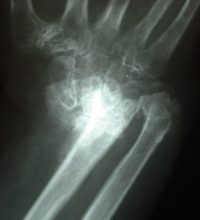

Εξαρθρήματα του καρπού, όπως είναι το εξάρθρημα του μηνοειδούς, η το διασκαφοειδές περιμηνοειδές εξάρθρημα, η βαρύτερη ίσως τραυματική βλάβη του καρπού με άμεση καταστροφή του χόνδρου, εκτεταμένη συνδεσμική βλάβη και διαταραχή της αιμάτωσης των οστών.

Η διάγνωση επιβεβαιώνεται με ακτινολογικό έλεγχο, αξονική και μαγνητική τομογραφία.